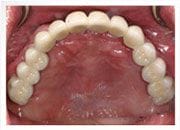

治療後

移民澳州的何先生,長期以來飽受缺牙之苦,原以為時常往來世界各地經商,無法好好的治療牙齒,下定決心植牙後,才知道原來植牙的療程並不複雜,也不需要耗費太多時間,要利用幾次休閒度假回台的時機,就輕鬆完成,全口的植牙重建。 現在,何先生每半年回台與我們笑談他品嚐世界各地美食的經驗。